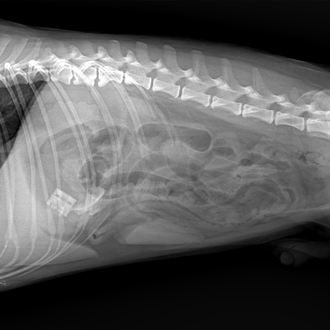

소화기계 수술

구토·식욕저하·복부 통증 같은 증상 뒤에 이물, 장폐색, 종괴 등 수술이 필요한 원인이 숨어 있을 수 있습니다.

정확한 진단 후 필요한 수술을 신중하게 진행합니다.